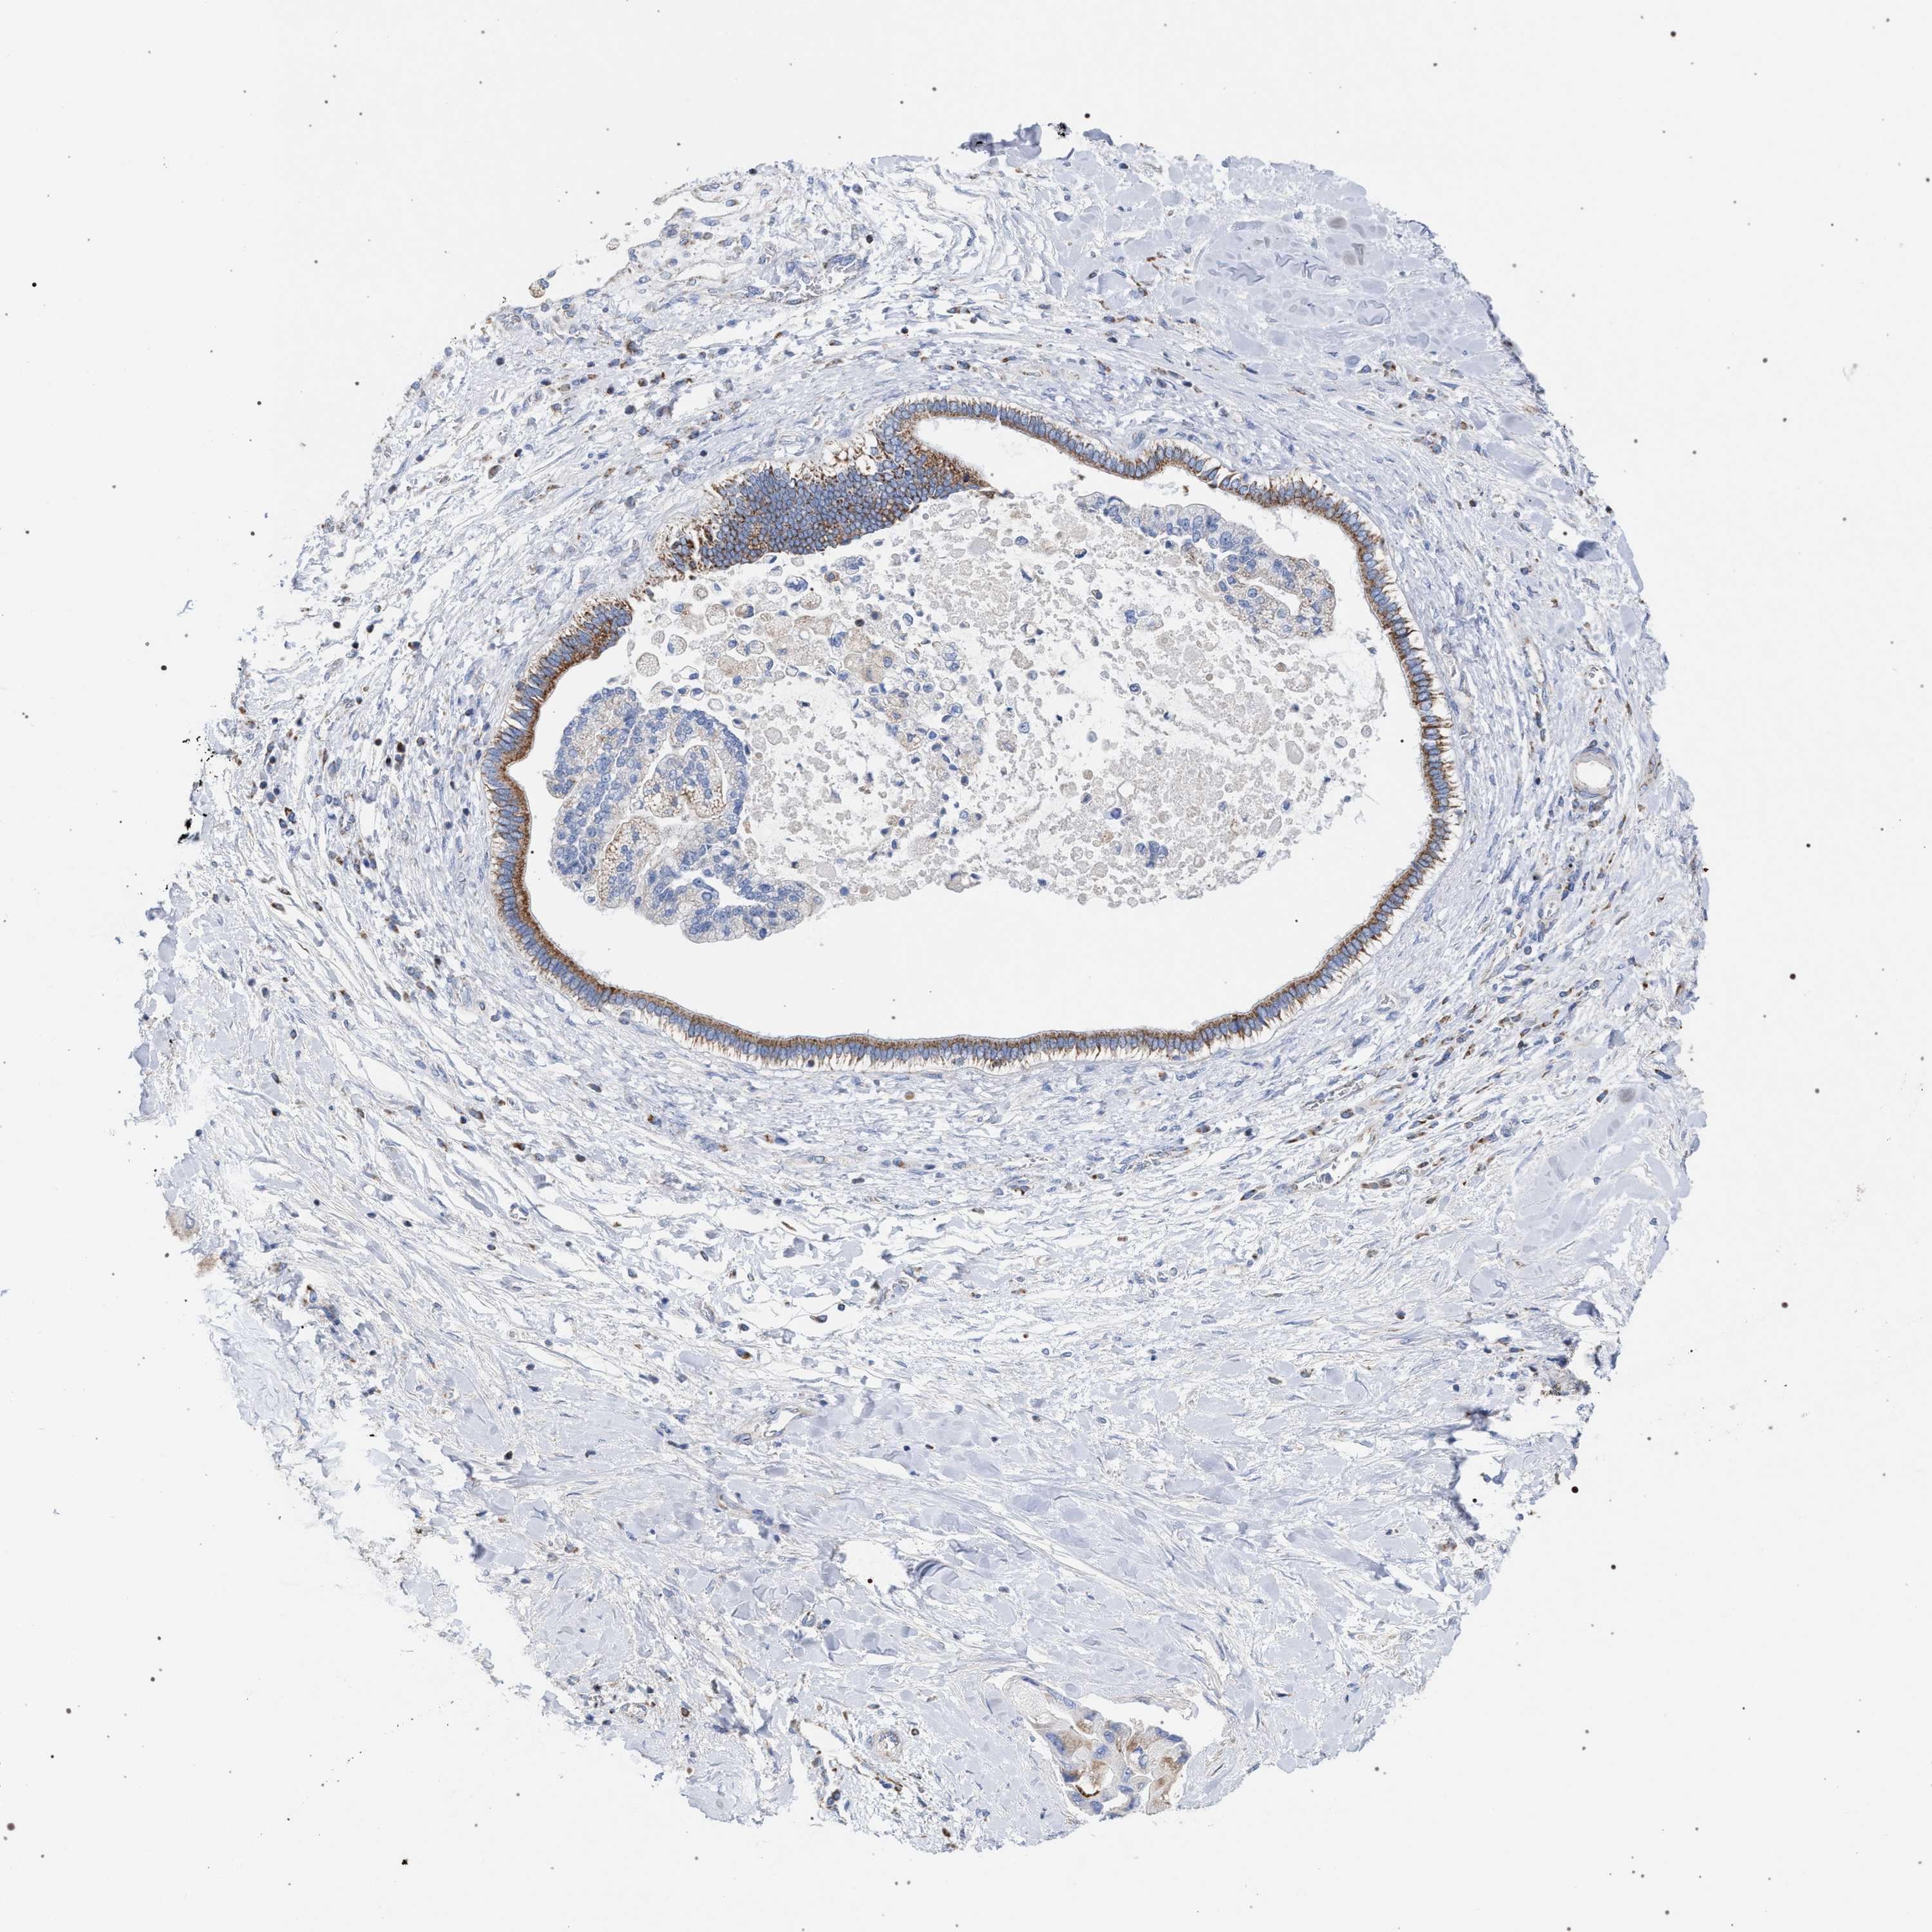

LIVER CANCER - Protein expressioni

A mouse-over function shows sample information and annotation data. Click on an image to view it in a full screen mode. Samples can be filtered based on level of antibody staining by selecting one or several of the following categories: high, medium, low and not detected. The assay and annotation is described here.

Note that samples used for immunohistochemistry by the Human Protein Atlas do not correspond to samples in the TCGA dataset.

Antibody stainingi

Antibody staining in the annotated cell types in the current human tissue is reported as not detected, low, medium, or high, based on conventional immunohistochemistry profiling in selected tissues. This score is based on the combination of the staining intensity and fraction of stained cells.

Each image is clickable and will lead to virtual microscopy that enables deeper exploration of all samples and also displays staining intensity scores, fraction scores and subcellular localization as well as patient and tissue information for each sample.

Antibody HPA022130

Antibody HPA031626

Staining

High

Medium

Low

Not detected

Intensity

Strong

Moderate

Weak

Negative

Quantity

>75%

75%-25%

<25%

None

Location

Nuclear

Cytoplasmic/membranous

Cytoplasmic/membranous,nuclear

Cholangiocarcinoma

Carcinoma, Hepatocellular, NOS